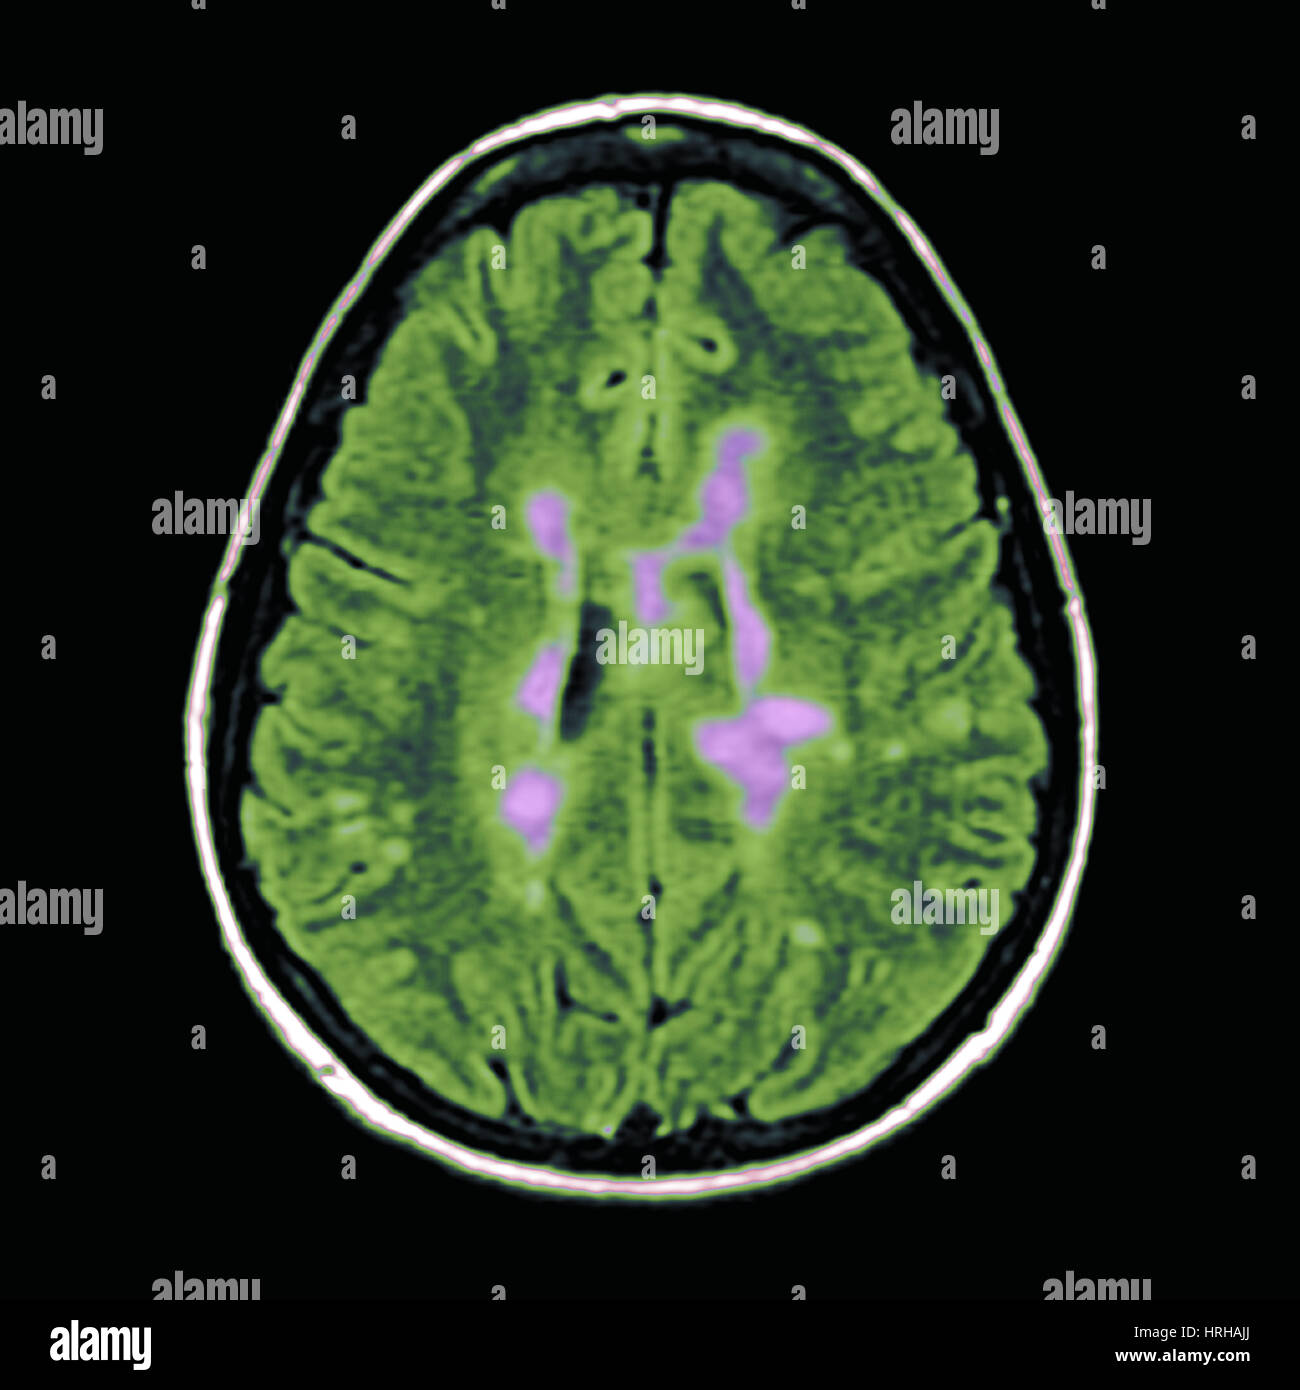

Multiple Sclerosis Mri Scan Multiple sclerosis, MRI brain scan

Multiple Sclerosis on MRI Stock Image C043/0443 Science Photo Library Can Multiple Sclerosis Be Seen On Mri You may receive an intravenous injection of a. — the emergence of advanced magnetic resonance imaging (mri) techniques, however, has revolutionized the detection of ms. — ms lesions are generally visible on mri scans from the earliest stages of the disease, and they may even be apparent before a person. — mri, which can reveal areas of. Can Multiple Sclerosis Be Seen On Mri.